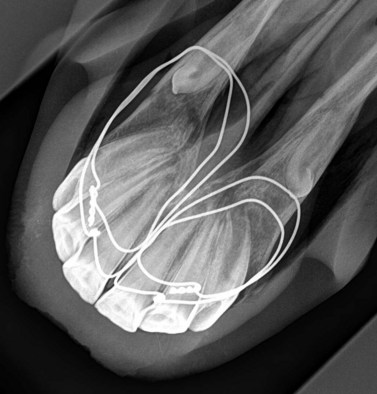

Fracture reduction in the young horse can usually be achieved through placement of single or multiple intra-oral tension wires attaching the avulsed portion to the caudal interdental space of the contralateral aspect of the mandible. Wires can be inserted via appropriate holes in the mandible drilled with a 2.7- or 3.2-mm Steinmann pin held in a hand chuck (Fig. 9.20) or by using an air drill (Fig. 9.21). Cannulation of the holes with a 14-gauge needle facilitates placement of the wire between teeth. A 14-gauge needle may be pushed through the softer mandibular bones of young foals without prior drilling of holes. At the completion of the procedure, the wire should pass through the fracture fragment, across the floor of the mouth, through the contralateral mandibular diastema then around the labial aspect of the rostral mandible (Fig. 9.22). The exact positioning of the anchoring holes will vary depending on fracture configuration and individual anatomical features. Wires are pressed digitally into the floor of the mouth to remove as much ‘slack’ as possible and to ensure they impinge as little as possible on the tongue. The ends are then brought together on the labial aspect of the mandible at a site distant to the fracture. Once the wire has been tightened and cut, it is necessary to protect the adjacent soft tissues from the sharp ends of the knot. A small amount of silicon polymer dental impression material, or acrylic bone cement can be affixed to the wire knot; alternatively, the tips of the wires can be sheathed with plastisol covers, which prevent labial abrasion.

Fig. 9.22 Simple rostral mandibular fracture stabilized.